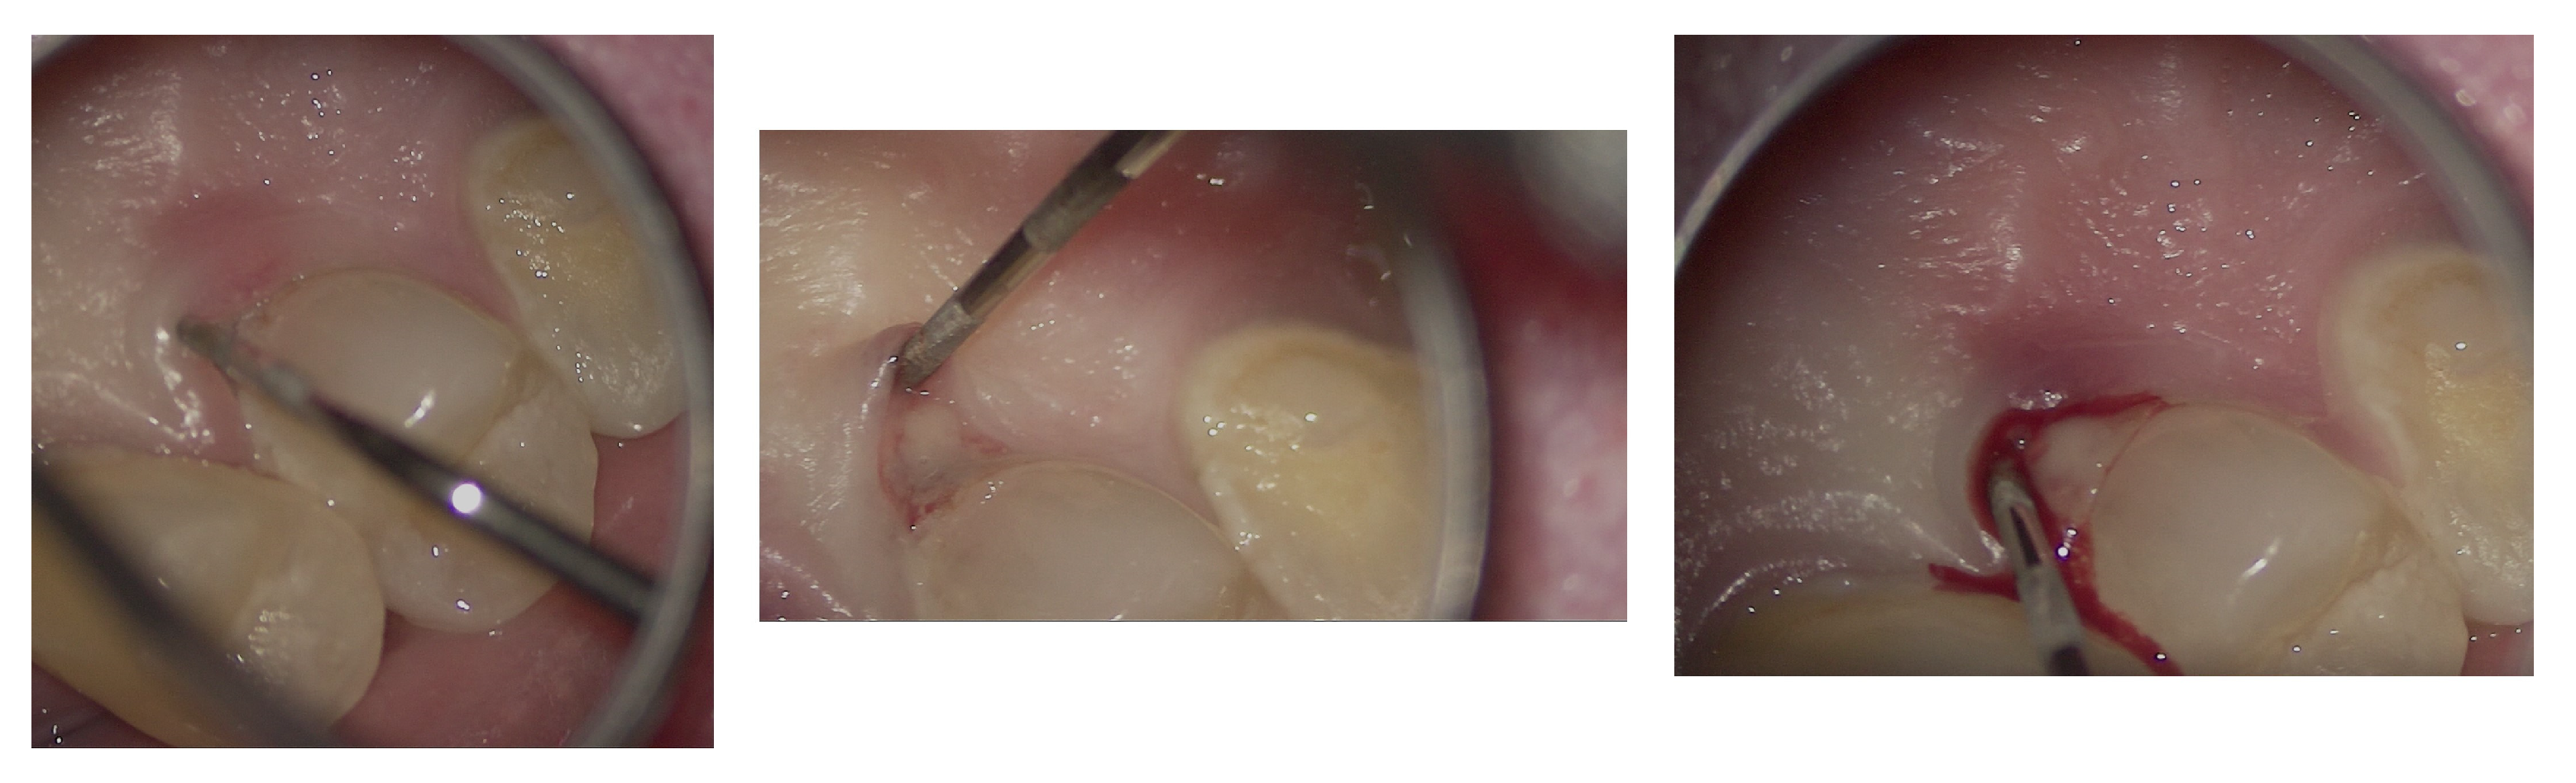

The entire procedure was performed under an operating microscope, Zumax 2380®, with an integrated HP camera (Zumax Medical Co., Ltd., Suzhou, China). In this case, the endodontic access cavity was prepared using a minimally invasive approach, aiming to preserve as much dental tissue as possible while ensuring adequate control and access to both the root canals and the cervical resorption lesion (Figure 6 and Figure 7).

Figure 6.

Microscopic exploration and probing of EPL under the operating microscope.